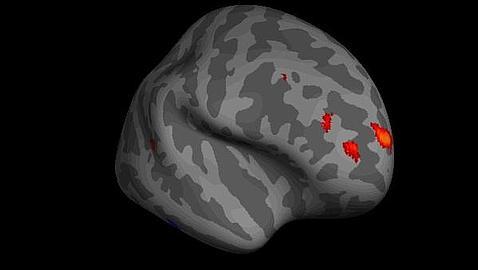

¿Por qué hay personas que, como suele decirse, se comen la cabeza, mientras que otras jamás meditan sobre lo que hacen? La respuesta parece encontrarse en una específica región del cerebro, que parece ser mayor en los individuos que reflexionan sobre sus pensamientos y decisiones, según un estudio del Centro Wellcome Trust de Neuroimagen en Londres (Reino Unido) que se publica en la revista Science.

Este acto de introspección, o pensar sobre los pensamientos propios, es un aspecto clave de la conciencia humana que varía mucho de una persona a otra. Los investigadores, dirigidos por Stephen Fleming, sugieren que el volumen de materia gris en la corteza prefrontal anterior del cerebro, que se encuentra justo detrás de los ojos, es un indicador fuerte de la capacidad introspectiva de una persona. Además, los autores señalan que la estructura de la materia blanca conectada con esta área está también vinculada a este proceso de introspección.

Los autores creen que en el futuro el descubrimiento podría ayudar a los científicos a comprender cómo ciertas lesiones cerebrales afectan a la capacidad de un individuo para reflexionar sobre sus propios pensamientos y acciones. Con este conocimiento, podrían desarrollarse tratamientos adaptados a los pacientes, como en el caso de las víctimas de ictus o aquellos con traumas cerebrales graves que podrían no comprender su propio estado.

El descubrimiento no significa necesariamente que los individuos con un volumen de materia gris mayor en esa región del cerebro hayan experimentado o vayan a tener más pensamientos introspectivos que otras personas. Pero los investigadores establecen una correlación entre la estructura de materia gris y materia blanca en la corteza prefrontal y los varios niveles de introspección que los individuos podrían experimentar.

No está claro, sin embargo, si estos descubrimientos reflejan las diferencias innatas en la anatomía humana, o bien, los efectos físicos de la experiencia y el aprendizaje sobre el cerebro. Esta última posibilidad plantea la perspectiva de que exista una vía para entrenar las capacidades metacognitivas al explotar la naturaleza maleable de estas regiones de la corteza prefrontal.